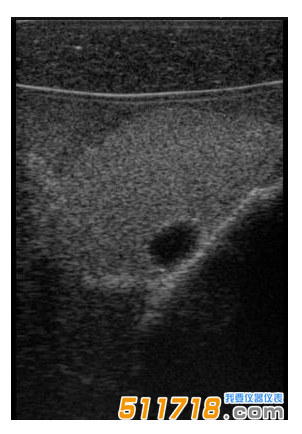

CIRS

074甲狀腺超聲訓(xùn)練模體包含一個(gè)略微擴(kuò)大的甲狀腺,位于一個(gè)擬人化的頸部。下巴和鎖骨被提供作為外部解剖標(biāo)志。體模提供氣管,頸內(nèi)靜脈和頸總動脈作為內(nèi)部解剖標(biāo)志。每個(gè)甲狀腺葉包含一個(gè)囊腫和一個(gè)等回聲僵硬病變。可以在甲狀腺內(nèi)定制生產(chǎn)各種結(jié)節(jié)。*有材料都配制成超現(xiàn)實(shí)的。

略微擴(kuò)大的甲狀腺包含單個(gè)囊腫和每個(gè)葉中的一個(gè)等回聲,僵硬的病變。

可以對每個(gè)囊腫進(jìn)行細(xì)針抽吸。每個(gè)僵硬病變都設(shè)計(jì)用于超聲彈性成像的可視化,并且可以進(jìn)行活組織檢查。這些病變對甲狀腺是等回聲的并且具有標(biāo)準(zhǔn)的B模式成像。

單純囊腫